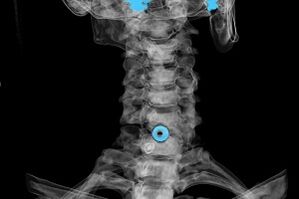

D'Diagnostik gëtt op Basis vu charakteristesche Symptomer etabléiert, wéi och mat:

- Röntgenstrahlen. D'Methode ass net effikass, virun allem an de leschten Etappe vun osteochondrosis Entwécklung.

- MRI (Magnéitesch Resonanz Imaging) vun der Gebärmutterhëllef. Eng Method déi Iech erlaabt Knochenstrukturen ze gesinn, herniéiert intervertebrale Scheiwen, hir Gréisst a Richtung vun der Entwécklung.

- Computertomographie. Eng manner effektiv Léisung wéi MRI, well d'Präsenz an d'Gréisst vun den Hernia ass schwéier ze bestëmmen.